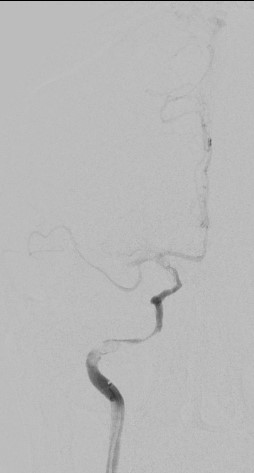

13:00 Больной подан в рентгеноперационную, выполнена церебральная ангиография: Ангиографические признаки атеросклеротического процесса брахиоцефальных артерий, тромботической окклюзии правой ВСА(Рис1), окклюзия левых ВСА(Рис3) и ПА(Рис2).

рис. 1 рис. 2